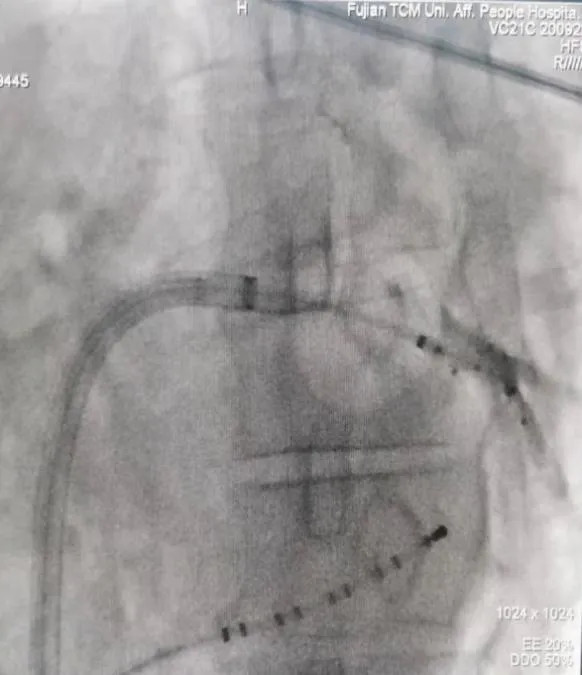

射頻消融術(shù)

三維電生理系統(tǒng)支持下的房性心動(dòng)過(guò)速射頻消融術(shù)

三維電生理系統(tǒng)支持下的心房顫動(dòng)+心房撲動(dòng)射頻消融術(shù)

房顫冷凍導(dǎo)管消融(陣發(fā)性房顫、高齡老人、心衰患者優(yōu)選)

長(zhǎng)程持續(xù)性房顫射頻消融術(shù)(環(huán)肺靜脈隔離+頂部線消融)